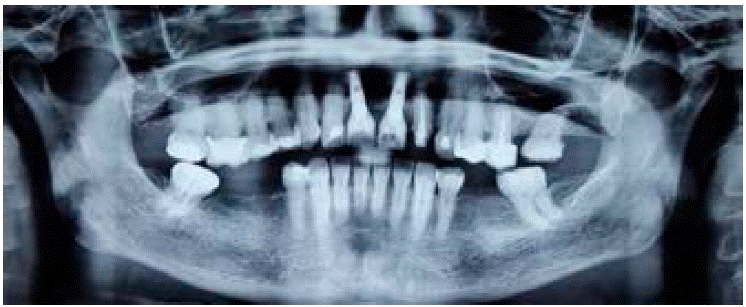

En el estudio radiográfico se corrobora la integra ción de los implantes en zona de 1.1 y 2.1, además de tratamiento de conductos en el diente 2.2 (Figura 2).